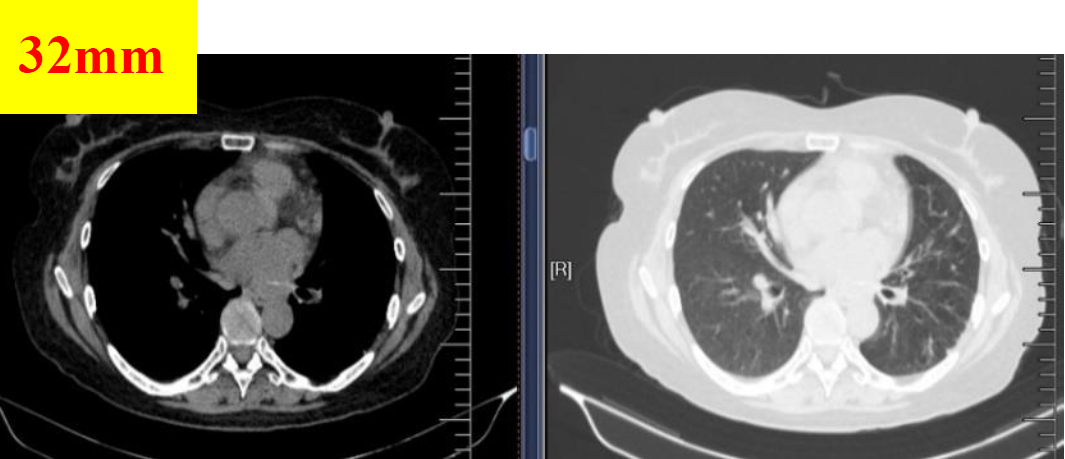

图5 2018.10.25影像学检查(PR)